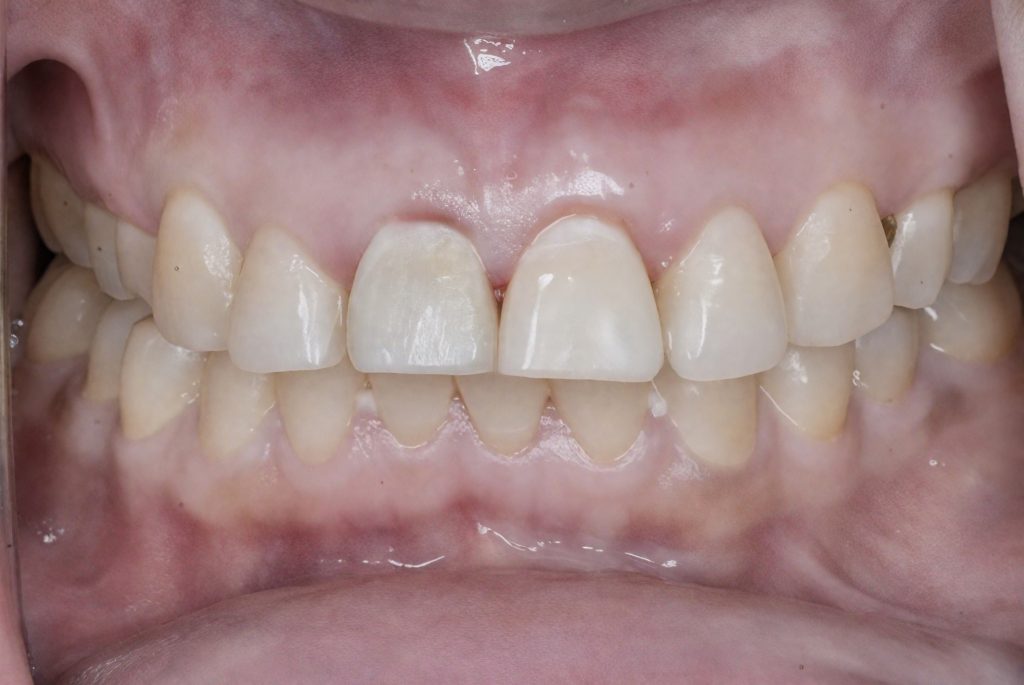

Deep dentin zones were rebuilt using GC EverX Posterior (fiber-reinforced dentin replacement) for internal toughness and crack resistance, followed by Tokuyama Estelite Sigma Quick for enamel layering (Fig 9–10).

Morphology and surface texture were sculpted under microscope vision to achieve natural light diffusion and line-angle harmony.

Final finishing was completed with Lucida polishing system + PoGo points, achieving high gloss and enamel translucency continuity.

- Anatomically accurate, lifelike composite restoration

- Patient asymptomatic and satisfied with the aesthetic outcome